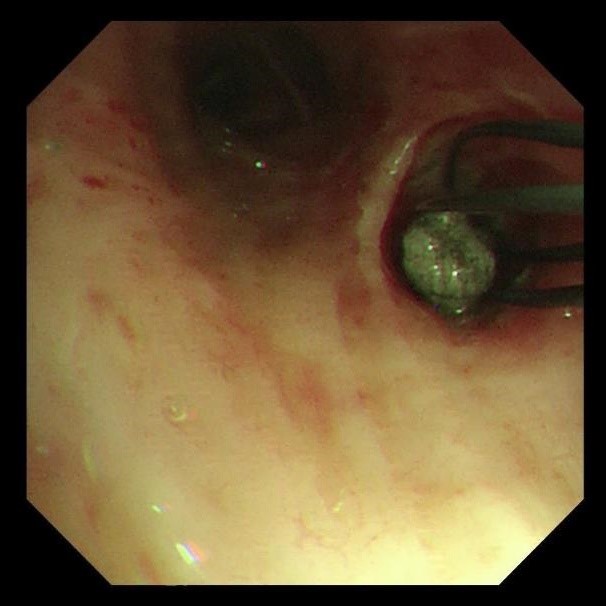

首次支气管镜清除手术:解决大块异物阻塞。因患者颈部有损伤,未行硬镜置入,在麻醉手术科的密切配合下,为患者经口插入8.5号气管插管,接呼吸机辅助通气,建立稳定的呼吸通道。随后,气管镜顺利进镜,发现气管及左主支气管内充满泥沙样分泌物、黄脓痰及块状异物。随后,实行精准操作:用吸引器清除泥沙样物质及黄脓痰;使用活检钳分次取出左下叶大块石状异物,并配合取石网篮清理;刷检带出细小碎石,并进行多部位生理盐水灌洗,最大限度清除可见异物。

两天后复查支气管镜,发现患者左下叶背段远端细支气管仍有残留泥沙样异物。团队采用超细支气管镜联合冷冻技术,通过冷冻探头将异物凝固,再用超细活检钳逐支清理,实现对远端气道的彻底清理,实现气道“零死角”。